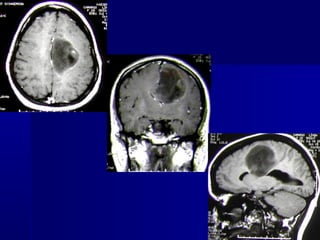

RECENTES AVANÇOS

O SURGIMENTO DA RESSONÂNCIA

MAGNÉTICA INTRAOPERATÓRIA

FACILITA CHECAR A COMPLETA

RESSECÇÃO DE TUMORES QUE SE

CONFUNDEM COM O TECIDO

CEREBRAL (GLIOMAS)